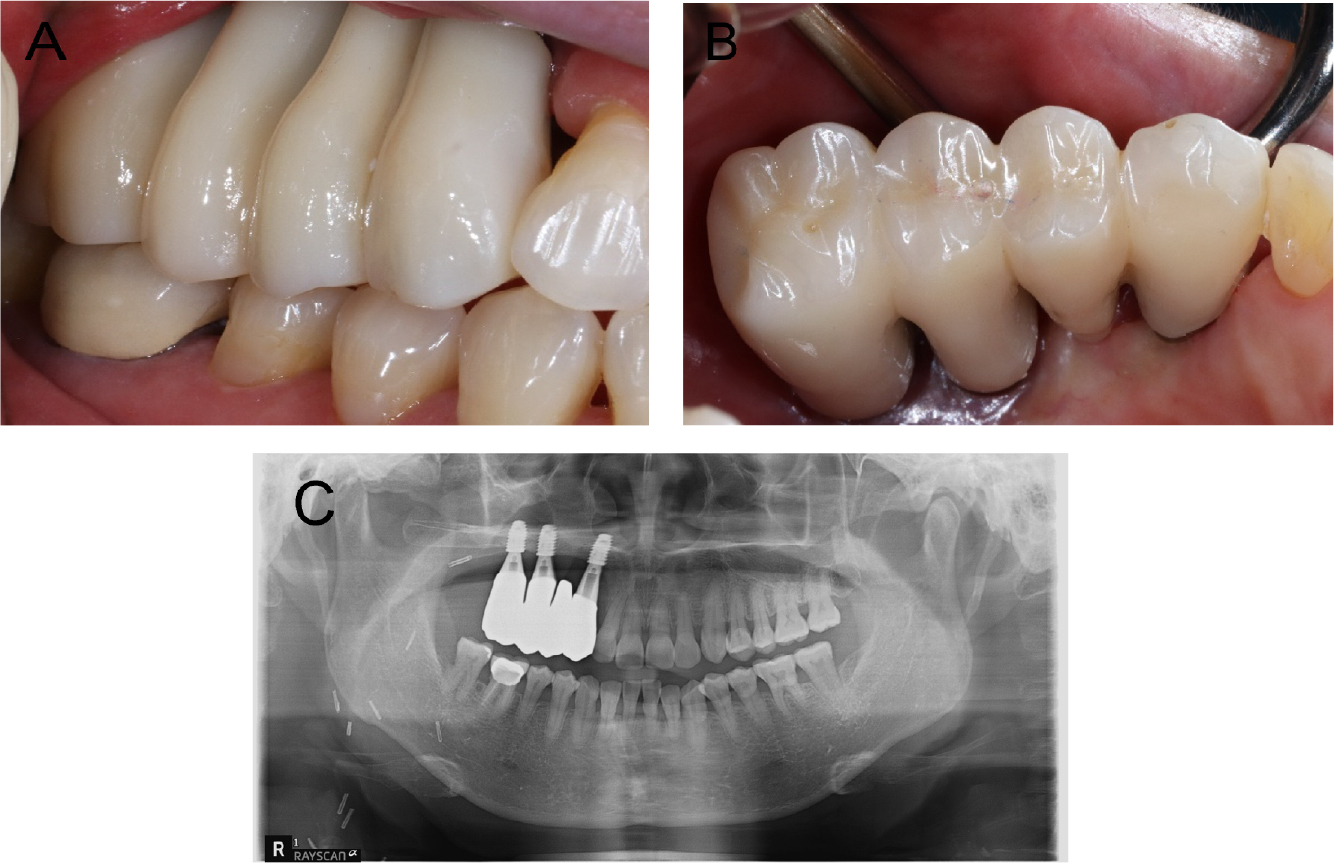

Conventional second-stage surgery was performed four months after the implant placement. Owing to the mucosal thickness, customized healing abutments were fabricated and connected to all the implant fixtures. Four months after the second-stage surgery, the implants were considered stable, and impressions of the provisional restoration were obtained. Impressions were made using an open-tray impression technique with pick-up impression copings and polyether impression materials (Impregum Penta; 3M ESPE, St. Paul, MN, USA). Five months after the second-stage surgery, customized abutments and a four-unit polymethyl methacrylate bridge were placed. During the provisional stage, the patients’ ability to adapt to the prosthesis and proficiency in maintaining proper oral hygiene were evaluated. After the prosthesis was placed, the patient reported difficulties in chewing on the right side and pronunciation problems. Over approximately four months, the patient gradually adapted to the provisional prosthesis. However, her oral hygiene management was poor, and persistent soft tissue inflammation was observed. Although toothbrushing instructions were provided at each visit, she had difficulty with cleaning the interproximal and pontic areas because of the long crown height. Therefore, to facilitate hygiene management, the customized abutment margin was positioned higher than the gingiva, and a new provisional prosthesis was fabricated with the prosthetic embrasure opened as wide as possible (Fig. 7). The patient used this new type of provisional prosthesis for approximately two months and visited the clinic for periodic check-ups. The patient adapted well to the new provisional prosthesis, and improvements were observed in her pronunciation, especially in affricate sounds and in her oral hygiene management skills. Additionally, she noticed an improvement in her chewing function, as she adapted to her new prosthesis. Once stable adaptation to the provisional restoration was achieved, a final prosthesis was fabricated, replicating the shape of the provisional prosthesis (Fig. 8).

Masticatory function is not simply performed by the teeth, but by a combination of organized groups of structures, including the lips, teeth, soft tissues, and muscles.18 The patient in this case may have developed a long-term unilateral chewing habit because of a defect caused by the maxillectomy, resulting in decreased masticatory function. In such patients, even if the implant is stable, it is preferable to undergo a provisional prosthesis phase rather than proceeding directly to the fabrication of the final prosthesis. By incorporating a provisional phase, the prosthesis can be easily modified based on patient adaptability and oral hygiene management. In this patient, masticatory function gradually improved over approximately four months of provisional prosthesis use. However, there are limitations in oral hygiene management and persistent gingival inflammation. Excessive crown height can result in inappropriate oral hygiene management and chronic inflammation.19 Therefore, the provisional prosthesis was modified to facilitate better hygiene management, leading to improved patient adaptation to the implanted prosthesis. After the delivery of provisional restorations, regular clinic visits and oral hygiene education sessions were conducted. After confirming that the patient adapted well to the provisional prosthesis, the final prosthesis was placed (Fig. 9). Thus, implant prostheses in patients undergoing reconstructive surgery can be a more predictive treatment when provisional prostheses are used, and periodic examinations and evaluations are particularly important.